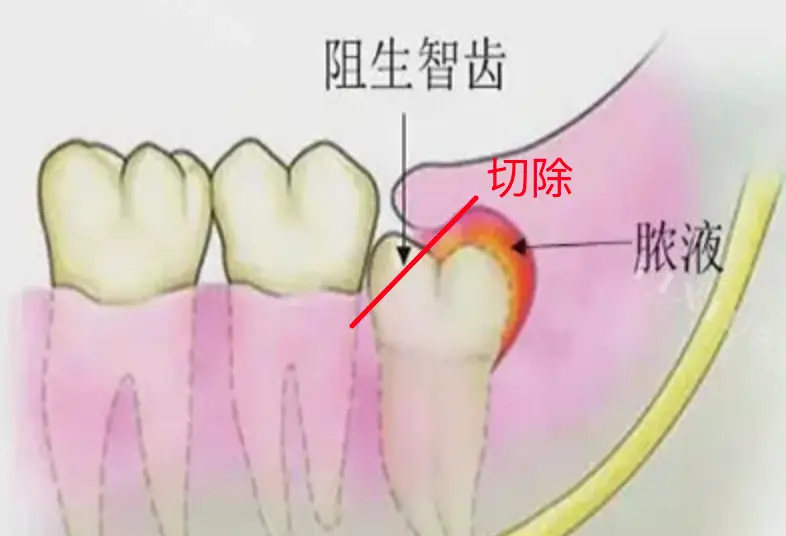

牙医说,我的(右下侧,牙片里是左下侧)智齿没有完全长出来,所以覆盖的牙龈和牙齿之间的缝隙很容易藏污纳垢。再加上我清洁不到位,所以就反复发炎。

Info

FYI,这就叫阻生齿